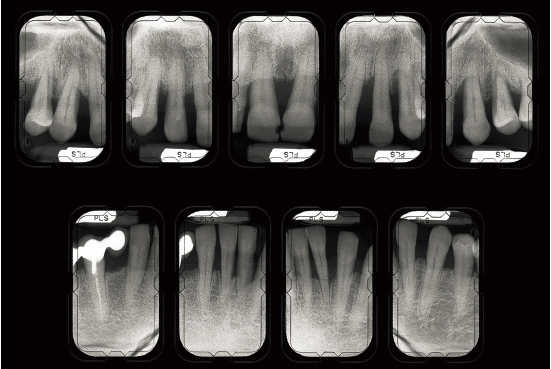

Fig 1-1a Aggressive periodontitis in a 40-year-old woman who is subject to stress and smokes one pack of cigarettes a day. The patient experienced an emotional shock 5 years earlier. A conventional treatment plan was initiated and included periodontal surgery throughout all quadrants. Professional maintenance (scaling and root planing) was carried out every 3 months, and the patient responded well.

Fig 1-1b Four years after treatment and maintenance therapy. Periodontal status has deteriorated in all areas. Observe the new attachment losses, dental migrations, and larger diastemata. It is clear that periodontal disease is not controlled. This patient’s disease was refractory to conventional treatment. Specific risk factors in this patient were underestimated.